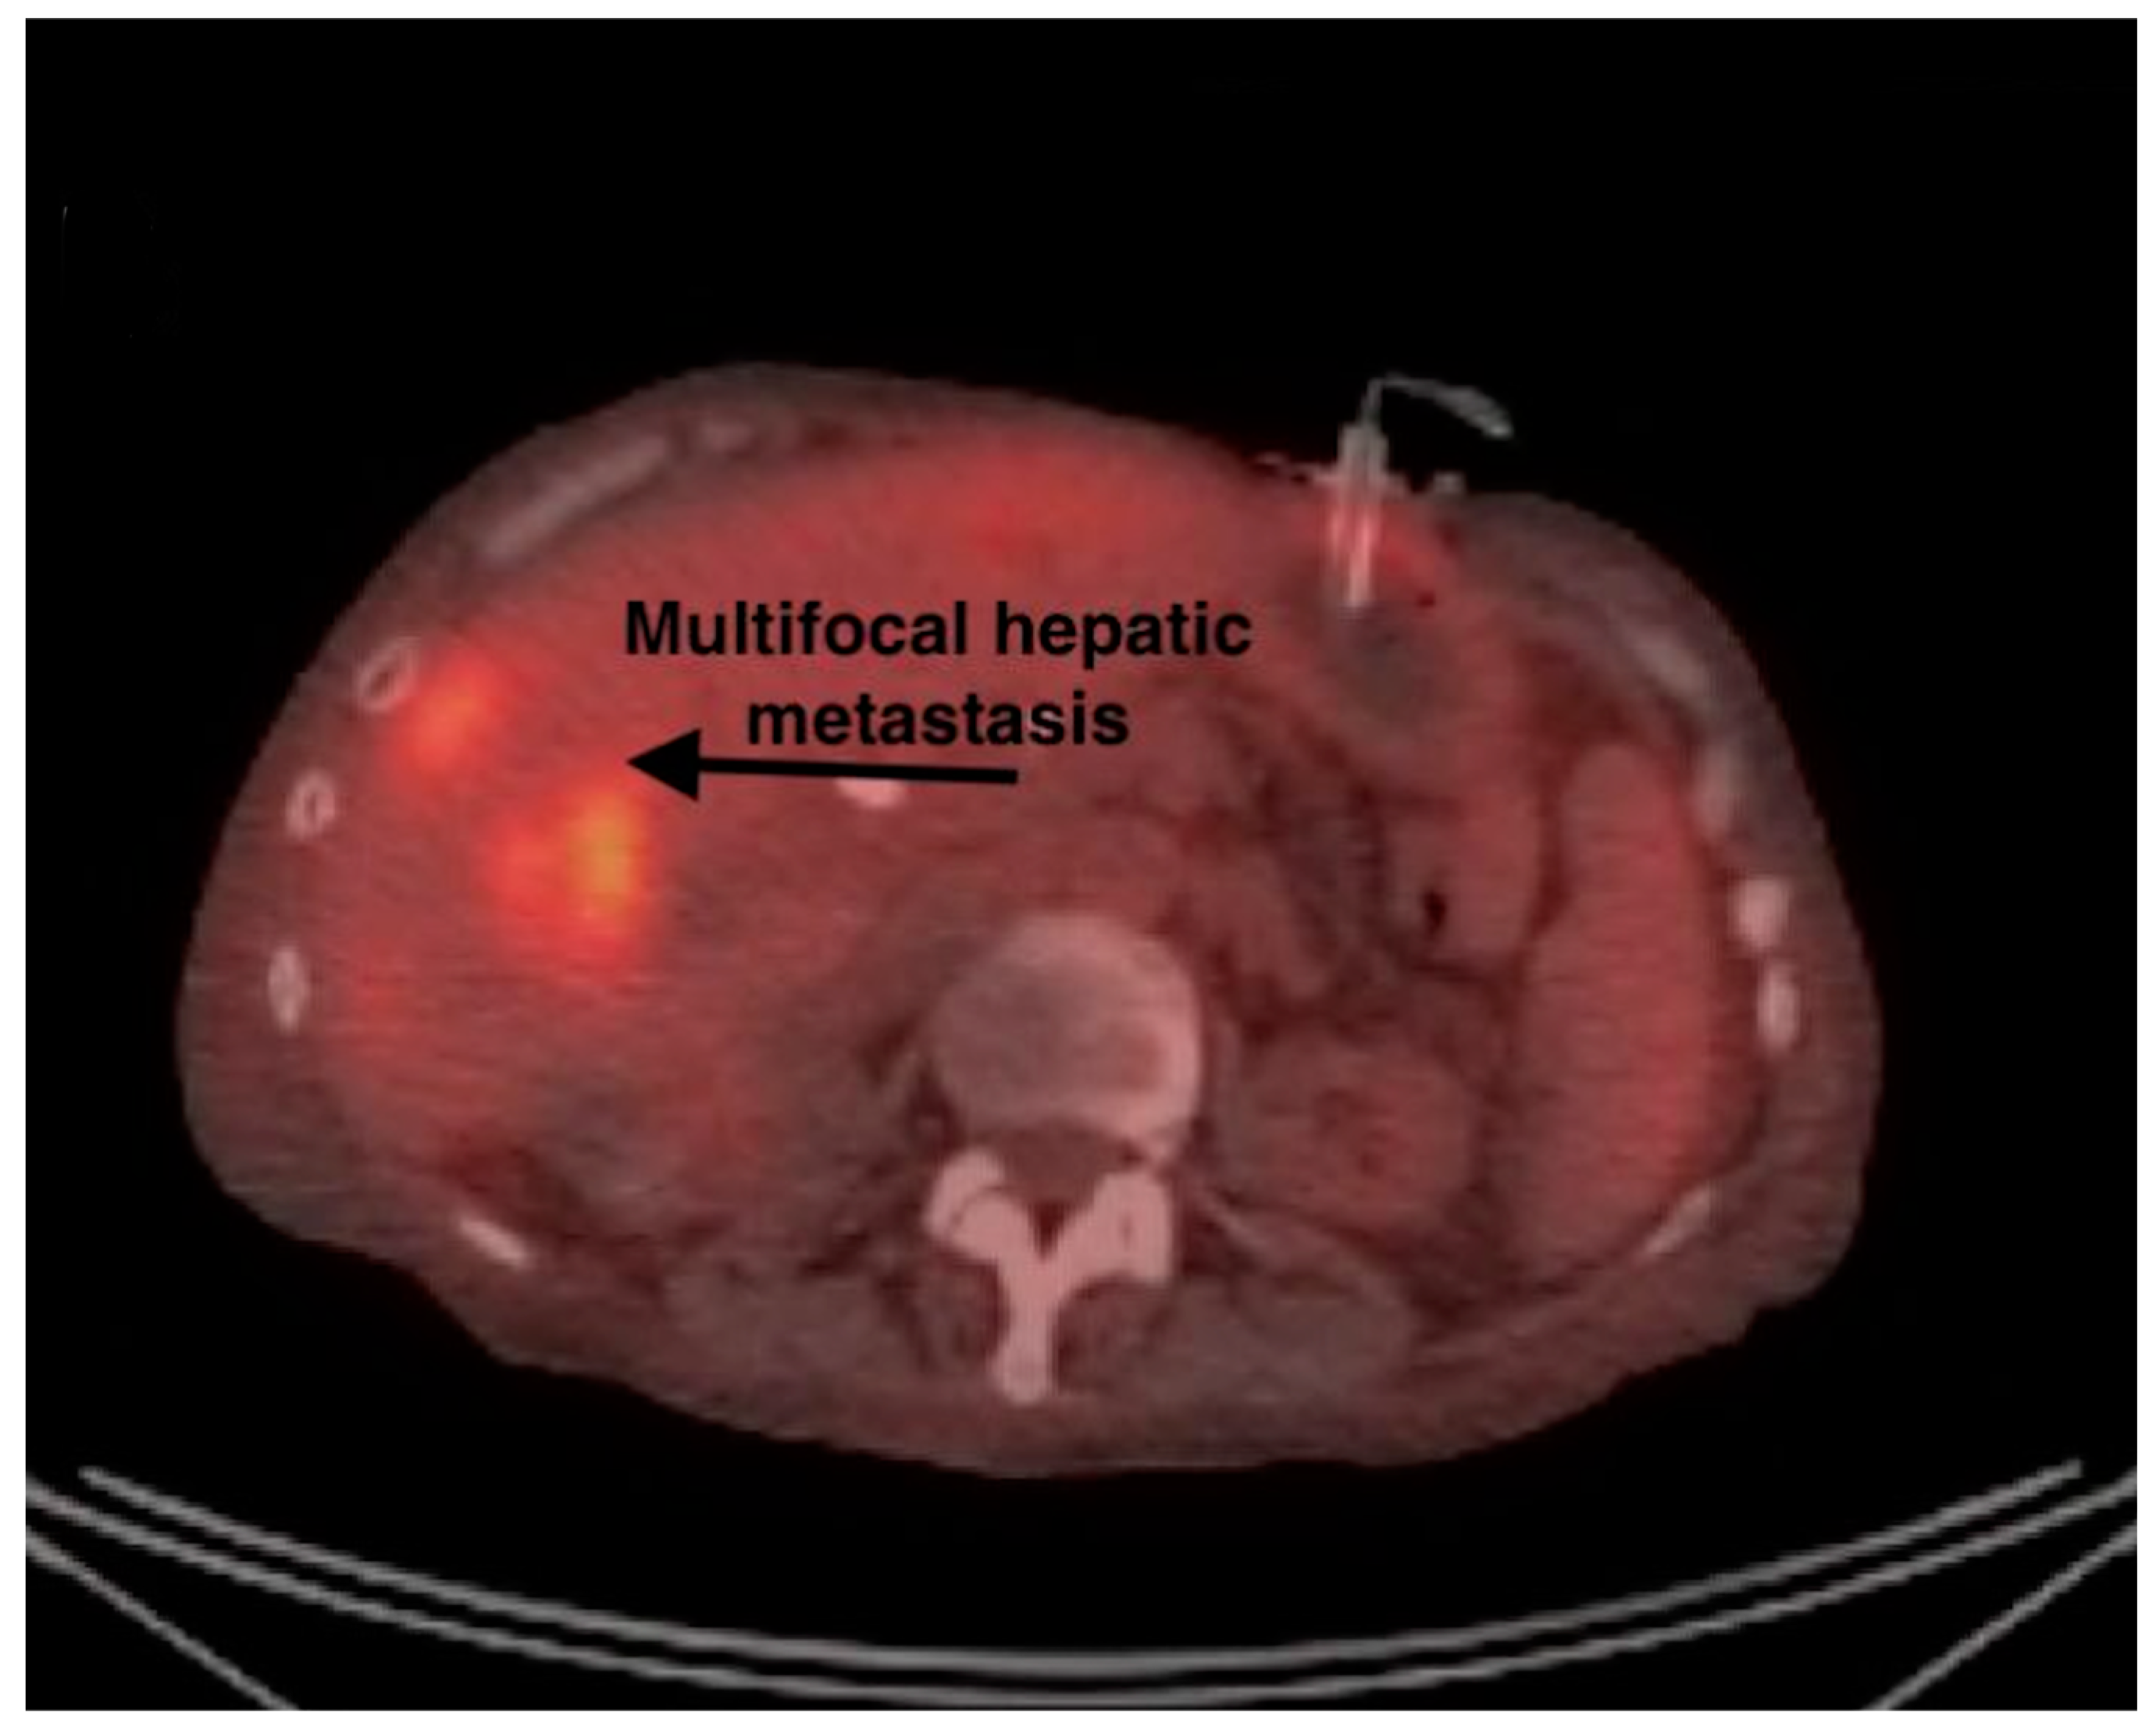

| 10 | PET-CT (Figure 2 and Figure 3) | Focal intense FDG uptake in the left upper quadrant in the small bowel loop and multifocal FDG avid hepatic metastasis. |